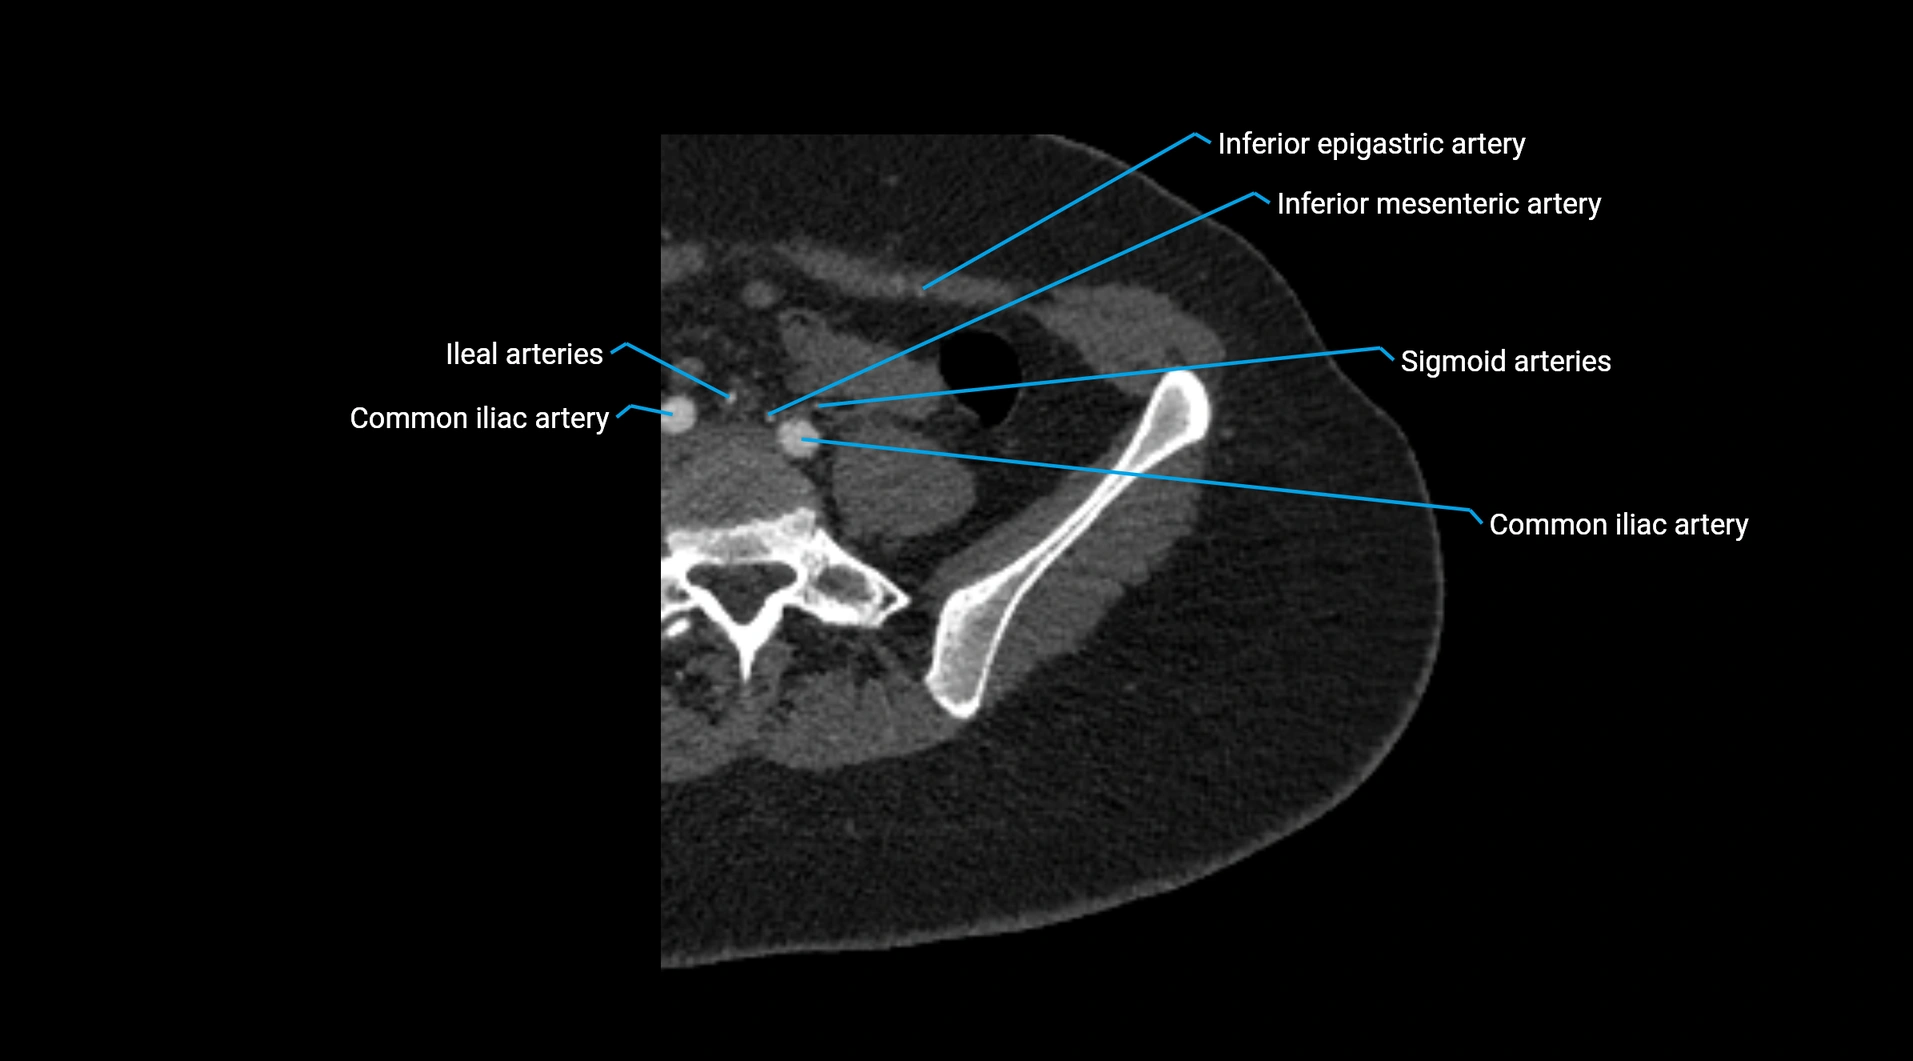

• Terminal branches: right and left common iliac arteries

Contrast-enhanced CT (CTA):

• Gold standard for abdominal aortic imaging

• Provides excellent detail of lumen, wall, aneurysm, thrombus, and branch vessels

• Multiplanar and 3D reconstructions help in aneurysm measurement, stent graft planning, and dissection evaluation

• Detects acute rupture, traumatic injury, or occlusion with high sensitivity